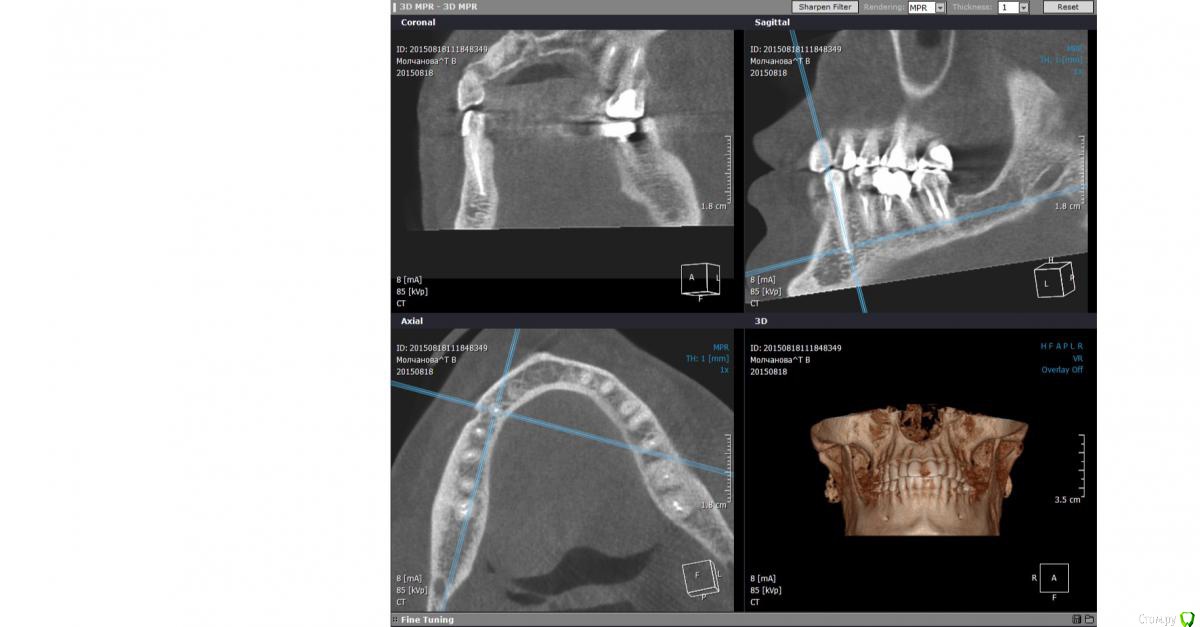

ТаняМ Опубликовано 31 октября, 2015 Поделиться Опубликовано 31 октября, 2015 Добрый день! Женщина, 41год. Истрия длится почти 8 месяцев. Заболела верхняя то ли 7 то ли 6 справа. На рентгене ничего подозрительного. 4 и 5 мёртвые давно. Долго не буду рассказывать, в общем каналы 6,7 также почистили и запломбировали. Очень долго болели опять же непонятно какие из них. Врач сказала, что проблемы со связками там есть, очистила ультразвуком несколько раз. Все прошло до июля. Опять начали ныть то ли 5,6 то ли 7. Чуть припухло около носа. Рентген-все чисто. Зачем то депульпировали нижнюю 4, врач решила, что это отраженные боли. Бестолку. Вскрыли 7 - чистили каналы, было дико больно, положили лекартство. Толку 0. Послали на КТ. Увеличина слизистая с правой стороны. Без жидкости. По зубам сказали все ОК. Сказали гайморит. Хотя никаких выделений из носа. Пропила антибиотики, промывания - толку 0. Боли сильные. Пошла к другому врачу. Вскрыли и 6. Опять прчистили все каналы, положили такую пасту коричневую - как смола и о чудо! Боли проходят, припухлость спадает. На простом пленочном рентгене увидели воспаление на 6, хотя КТ его не показало. Ходила 4 недели, меняли лекарство. На последнем (с камфорой) опять стало поднывать. Врач пломбирует каналы 7. Все ок. Не болит. Через неделю, проверяет каналы 6, говорит все отлично, каналы сухие, здоровые, плобирует каналы 6. При пломбировке было больновато. На след. день опять ноющая боль и небольшая припухлость. Короче, прошло 3 недели. Сильные боли опять то ли 7,6,5? Утром встаю прямо как жидкость возле носа справа. И боль щека, нос справа. Боль отдаёт в челюсть, под глаз, ухо. На десне в проекции этих зубов как болячка небольшая. Болит очень голова постоянно. Рентген пазух, осмотр Лора - гайморита нет. Рентген 6,7 - пломбировка отличная. Просила открыть 6-ку. Колят траумель в десну и говорят, что больше туда не полезут, только если удалять зубы, т.к. с их стороны ничего не видят и сделано по максимому. Оба зуба, забыла сказать, корнями находятся в гайморовой. Что мне делать? Это какой-то 3-х месячный ужас. Что посоветуете? Спасибо большое. Снимки после пломбировки прилагаю. Ссылка на комментарий

Larnary Опубликовано 31 октября, 2015 Поделиться Опубликовано 31 октября, 2015 (изменено) По вашему анамнезу и тем снимкам,что вы нам предоставили можно предположить выход паркана(раствор для промывания каналов) за верхушку корня в пазуху. Но это пока только версия. Ждем оптг или кт Изменено 31 октября, 2015 пользователем Larnary Ссылка на комментарий

ТаняМ Опубликовано 31 октября, 2015 Автор Поделиться Опубликовано 31 октября, 2015 Вот на всякий случай скрины КТ до повторных перепломбировок. Может там тоже что-то увидеть можно? Ссылка на комментарий